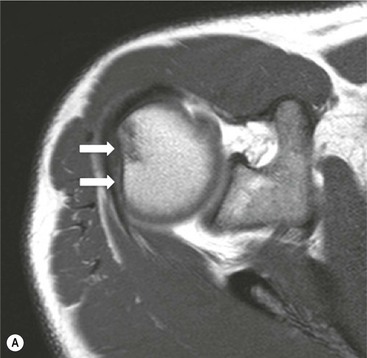

The primary sign of a rotator cuff FTT is a focal deficiency of the tendon (Figs. 46-4 and 46-5). This nearly always occurs at the tendon insertion on the tuberosity. The margins of the tear are best delineated when there is fluid within the tendon defect. Secondary signs of an FTT include the presence of fluid in both the GHJ and SAB, and flattening or concavity of the subacromial fat plane.

PTTs are less reliably demonstrated by both MRI and US, and it may be difficult to differentiate tendinopathy from partial tears. Focal clefts, tears, or tendon thinning affecting the articular margin of the footprint of the tuberosity are most common (Figs. 46-6 and 46-7). Tendon thickening is not always present. It is important not to mistake magic angle phenomenon on short TE MR sequences or anisotropy on US as evidence of tendinopathy.2